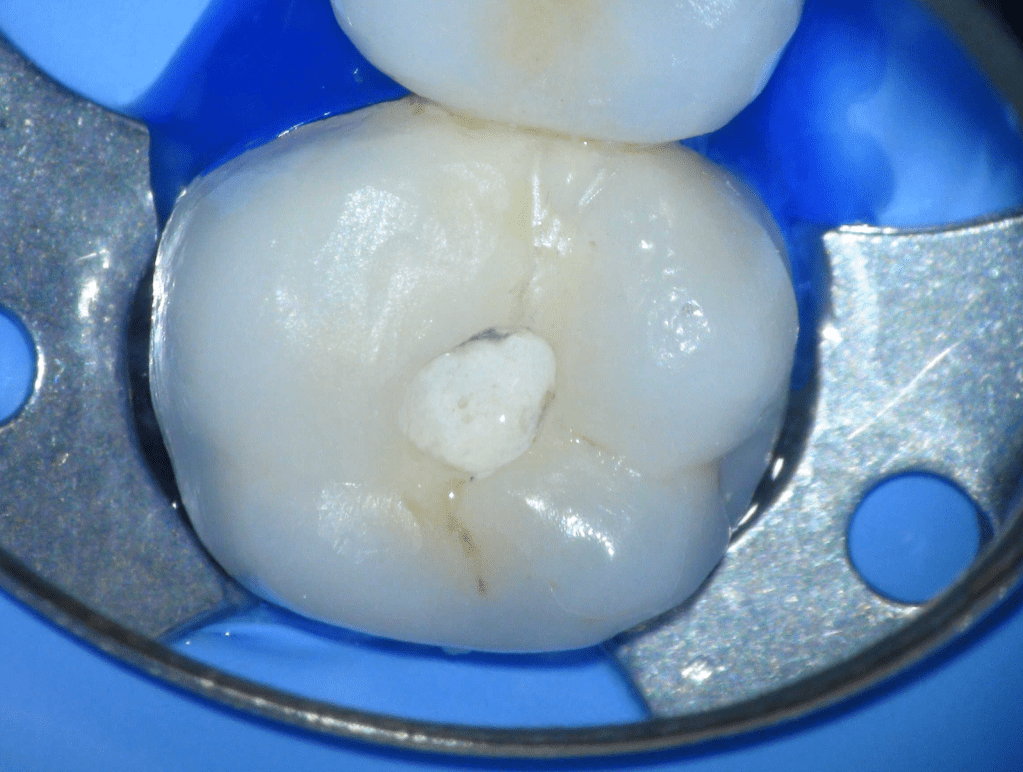

Fisura, remoción amalgama para explorar